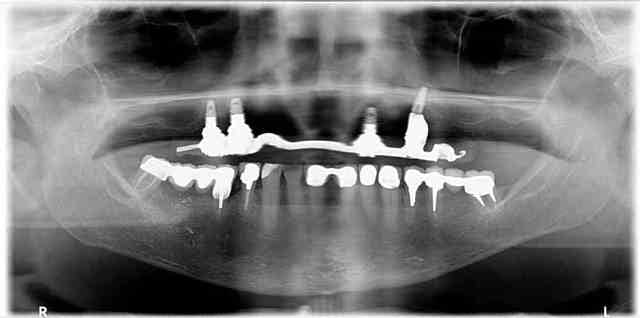

Et pour illustrer mes propos voici quelques photos issus du book of horror que je suis en train de me constituer.

Quand vous tombé là-dessus, quelle est votre réaction? Et surtout quand ça a été commis dans votre propre cabinet pour une somme indécente. Le patient vous demande de finir le travail alors qu'il a déjà dépenser une fortune pour ce résultat. Et il faut prendre en compte le fait que des patients dans cet état j'en ai des dizaines elle que le gars qui a fait ça n'a en aucun cas l'intention de rembourser quoi que ce soit.

Vous voyez, on est loin du niti pété ou de la couronne débordante... Et le monsieur est expert devant les tribunaux...